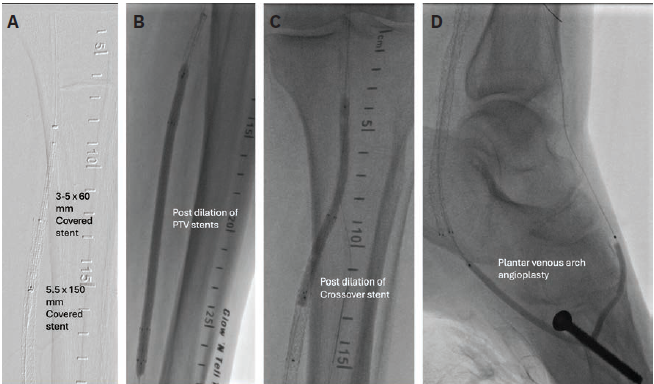

peripheral balloon (Figure 3B). Repeat angiography indicated a potential crossover segment at the proximal posterior tibial artery. A 5 mm x 100 mm peripheral balloon was advanced from the left lateral plantar vein to the left cranial posterior tibial vein to cross over the segment, and was dilated to mark the posterior tibial vein. Using the ARC device (LimFlow), the Nitrex wire (Medtronic) was crossed from the posterior tibial artery to the posterior tibial vein under fluoroscopy guidance (Figure 3C). The posterior tibial artery-posterior tibial vein crossover site was dilated with a 3.5 mm x 120 mm balloon (Figure 3D). Vector valvulotome (forward-cutting) (LimFlow) was used to destroy the valves of the posterior tibial vein. The posterior tibial vein-lateral plantar vein was stented with 5.5 mm x 150 mm (LimFlow) covered stents (two stents were placed) (Figure 4A). The posterior tibial artery-posterior tibial vein crossover site was stented with a 3.5 mm x 60 mm tapered covered stent (LimFlow) (Figure 4A). The stents were dilated with a 5.0 mm x 150 mm peripheral balloon in the venous segment and a 3.5 mm x 120 mm peripheral balloon in the arterial segment (Figures 4B-C).

The Nitrex wire was removed, and the plantar venous arch was crossed with a Command 14 wire and CXI microcatheter. The arch was dilated with a 3.0 mm x 80 mm peripheral balloon, and the lateral plantar vein sheath was removed, achieving hemostasis simultaneously (Figure 4D). The final angiogram demonstrated brisk flow through the TADV covered stent graft to the plantar venous arch without any flow-limiting residual stenosis, dissection, or perforation (Figure 5). Complete wound healing occurred over six months with extensive podiatry care (Figure 6).